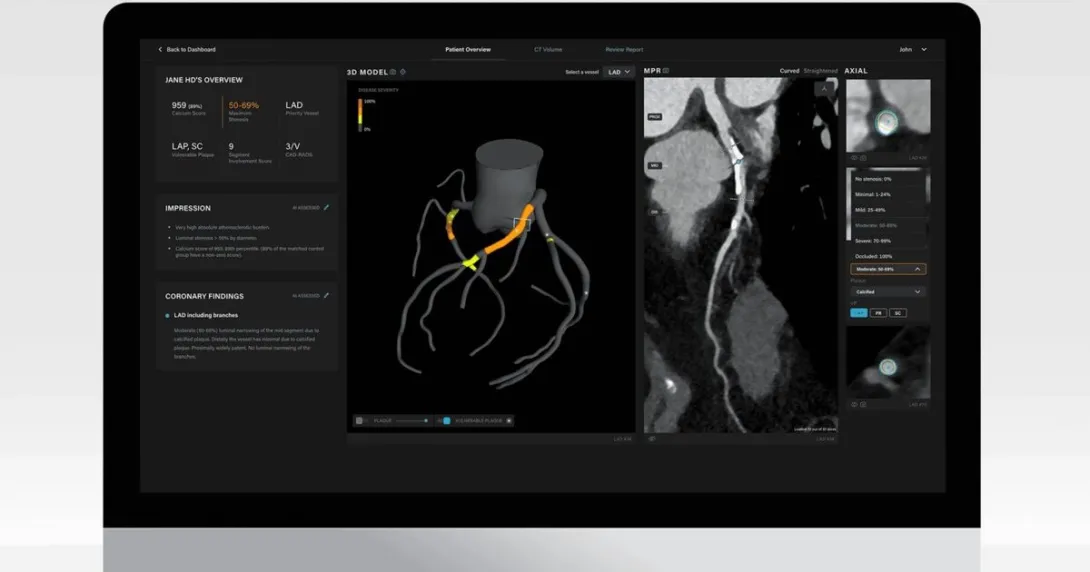

The Artrya Salix is an AI-powered software that analyses cardiac CT scans, detecting atherosclerotic plaque, which is a substrate of most heart attacks. It reports within 15 minutes an assessment of a patient's vulnerable plaques, stenosis, calcium score and total plaque burden.

The Heart Center Research division of the Huntsville Heart Center will conduct a multi-scanner retrospective study to validate the AI behind Artrya Salix. It will use previously obtained CT scans that will be anonymised and uploaded to Salix. Its interpretation will then be compared against the interpretation of recruited expert readers.

Dr Michael L. Ridner, cardiologist and principal investigator of the study, said his team will compare the heart scans "to see if we can validate the accuracy of Artrya Salix AI software in identifying coronary artery disease, specifically high-risk plaque, as compared to human readers".